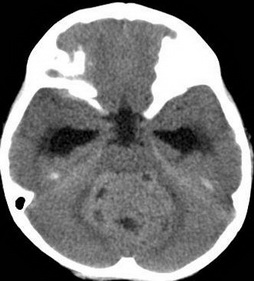

入院的当天,微侵袭神经外科的吴杰主任为阳阳完善了所有的检查及术前准备,并急诊实施了右侧脑室钻孔外引流术。术后阳阳复查,颅脑MRI提示:1、小脑蚓部占位性病变,考虑髓母细胞瘤可能性大(如图1);2、幕上梗阻性脑积水,并脑室周围间质性水肿(如图2);全脊髓MRI提示:胸腰段软脑膜线样高信号影,考虑肿瘤种植转移(如图3)。

图1:小脑蚓部占位病变,CT呈等或略高密度影;脑室系统扩张;